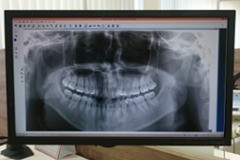

院内にはCT画像診断センターを備えており、骨量や神経・血管の位置などを立体的に確認することが可能です。また、Sim/Plantというシミュレーションソフトを活用することで、インプラントの埋入位置や必要な骨造成量を事前に把握できます。これにより、安全性を高めながら、ひとりひとりの状態に合わせた治療計画を立てられます。

診療スペースには、マイクロスコープ対応の診察ユニットをはじめ、患者様のストレスを軽減する設計のチェアや衛生管理システムが導入されています。診断面では、デジタルレントゲンを用いることでX線の被ばく量を最小限に抑えつつ、撮影した画像をモニターですぐに確認できる体制です。従来のフィルムタイプと比較して最大95%の被ばく量削減が可能とされています。